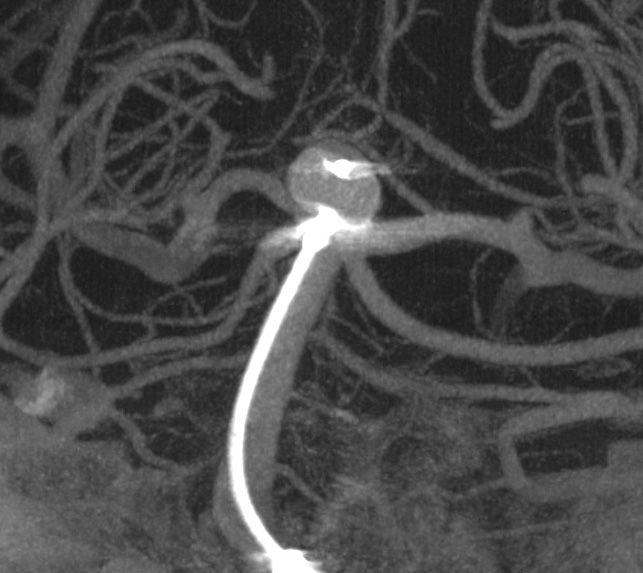

脳底動脈瘤にWEBを誘導する